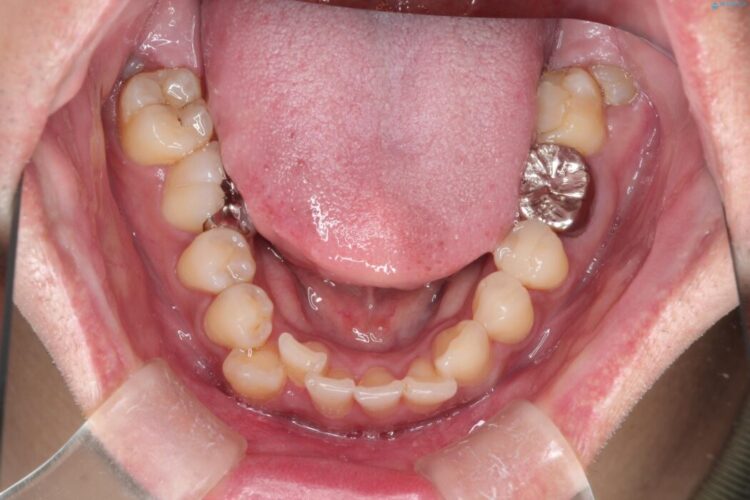

右上の八重歯と、下の歯の凸凹を治したいとご来院されました。

上顎右側第一小臼歯と下顎右側第一小臼歯を抜歯しワイヤー矯正を行いました。

噛み合わせのズレが右側で大きかった(2級)ため、右側上下2本の歯を抜歯し、ワイヤー矯正で噛み合わせを左右対称の理想的な位置に改善しました。